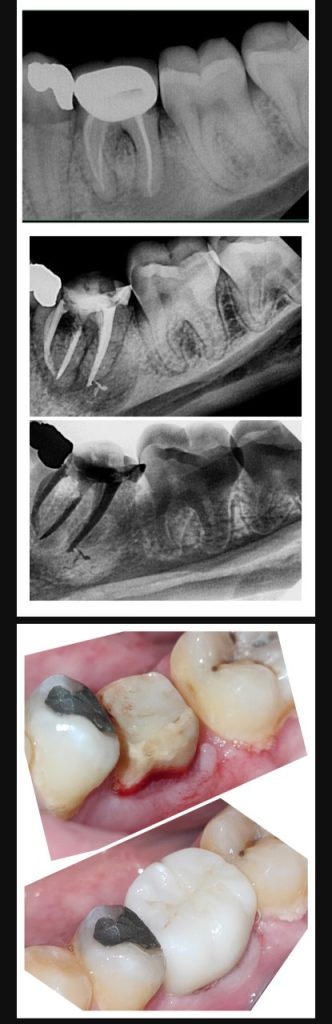

Retreatment of LL6

Phase I

– Periapical radiolucency related to poor RCT

– poor fitting crown and destroying biological width

Phase II

– removal of the crown and begin RC retreatment removing old gutta percha and disinfect all RC system for two visits then sealed

Phase III

– surgical crown lengthening were done to regain ferrule effect

Phase IV

– Verti-prep for the crown to save tooth structure

* Final image one mouth later*